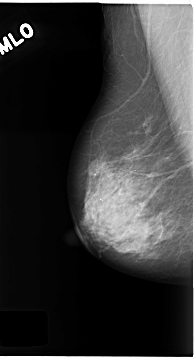

C_0180_1.RIGHT_MLO

C_0180_1.LEFT_MLO

RIGHT_CC LINES 4680 PIXELS_PER_LINE 2600 BITS_PER_PIXEL 12 RESOLUTION 50 NON_OVERLAY

RIGHT_MLO LINES 4688 PIXELS_PER_LINE 2520 BITS_PER_PIXEL 12 RESOLUTION 50 NON_OVERLAY